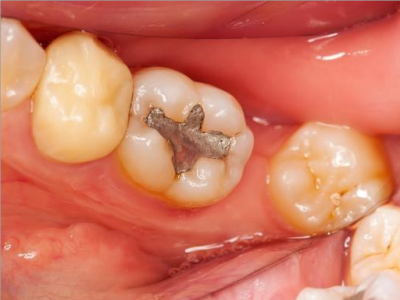

牙龈

肿 · 化脓

智齿冠周炎牙龈肿起来图

智齿冠周炎患者的智齿上有黑点,相邻的牙齿也有黑斑出现,龋齿已经形成。牙龈处发红发肿,局部化脓,且脓液增多,自觉有跳痛,需要立即就医。